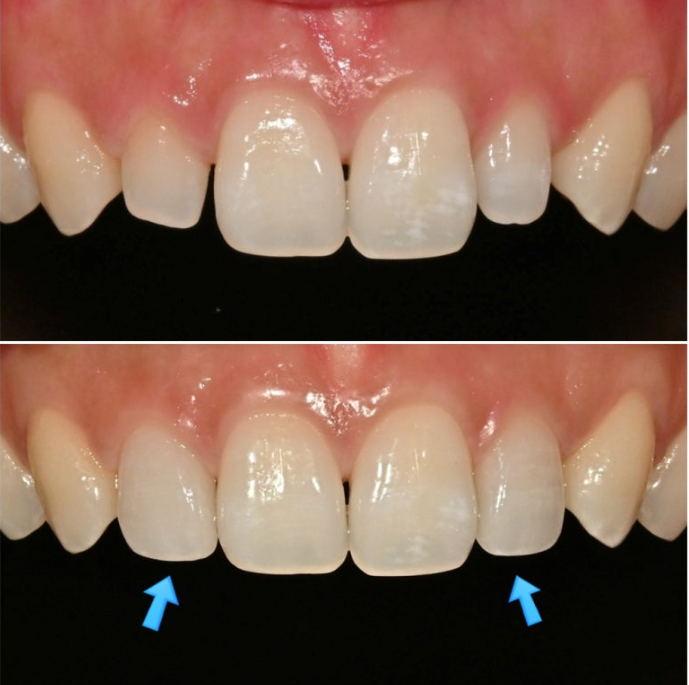

자 그렇다면 반점치가 남은 상태에서 최대한 이질감 없게끔 왜소치 라미네이트가 들어가야겠죠?

이 경우 라미네이트에 약간 반점치스러운 무늬를 일부러 약하게 넣어서 이질감을 없애고 극도의 자연감을 살립니다.

표면의 아주 옅은 반점치 무늬가 보이시나요?

주변 치아와 질감 뿐 아니라 표면의 미세 무늬까지 구현하여 이질감을 없애 자연스럽게 어우러지도록 합니다.